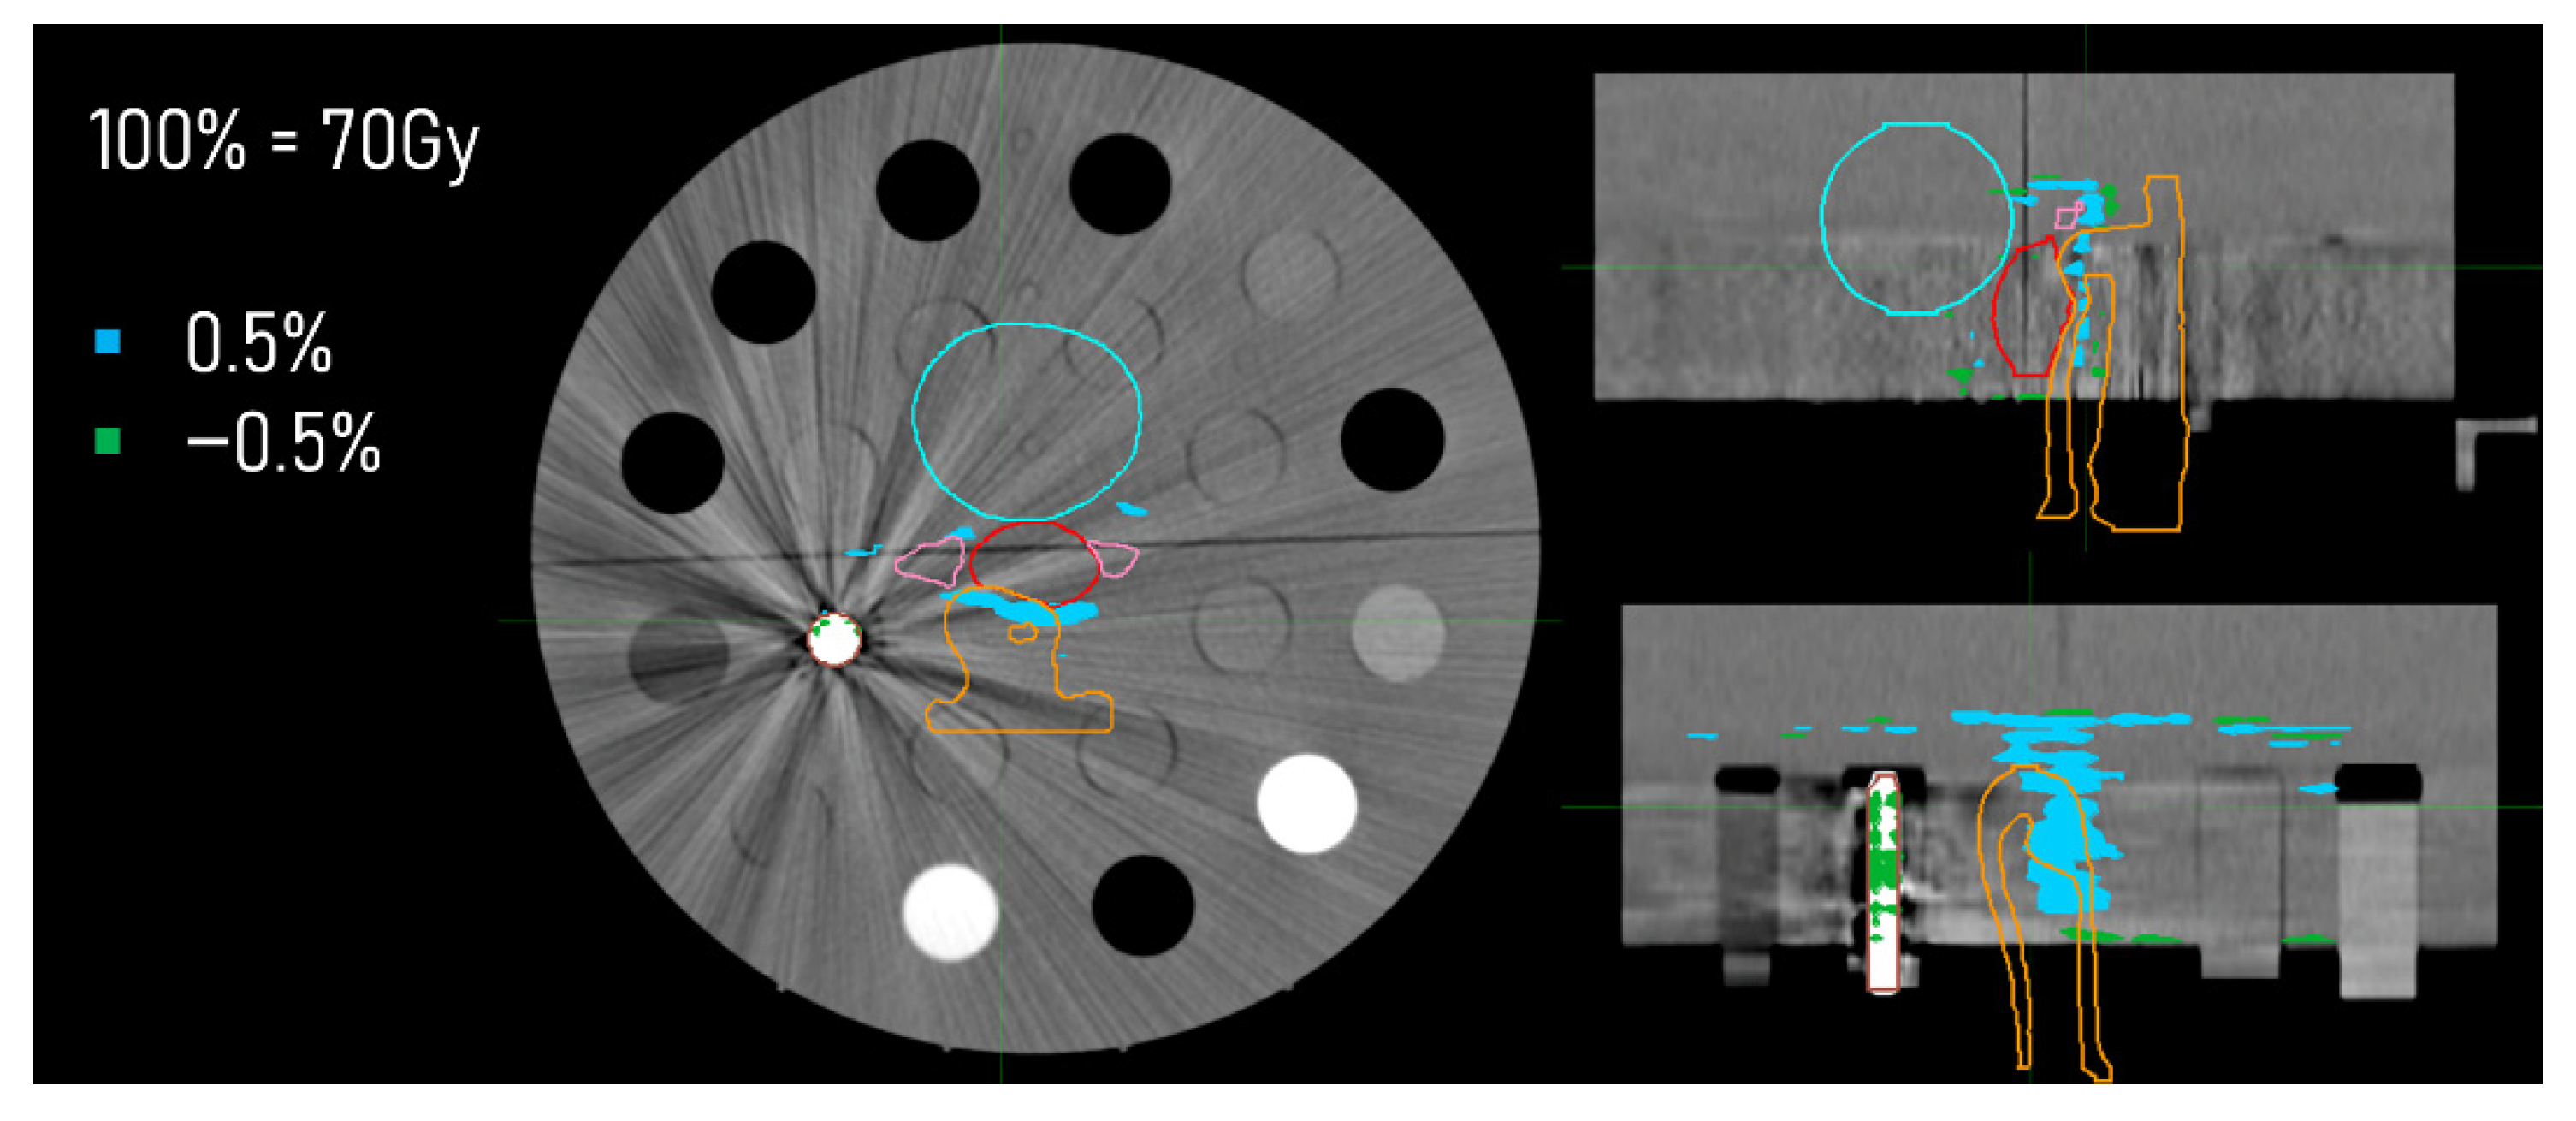

3.3. Dose Distributions